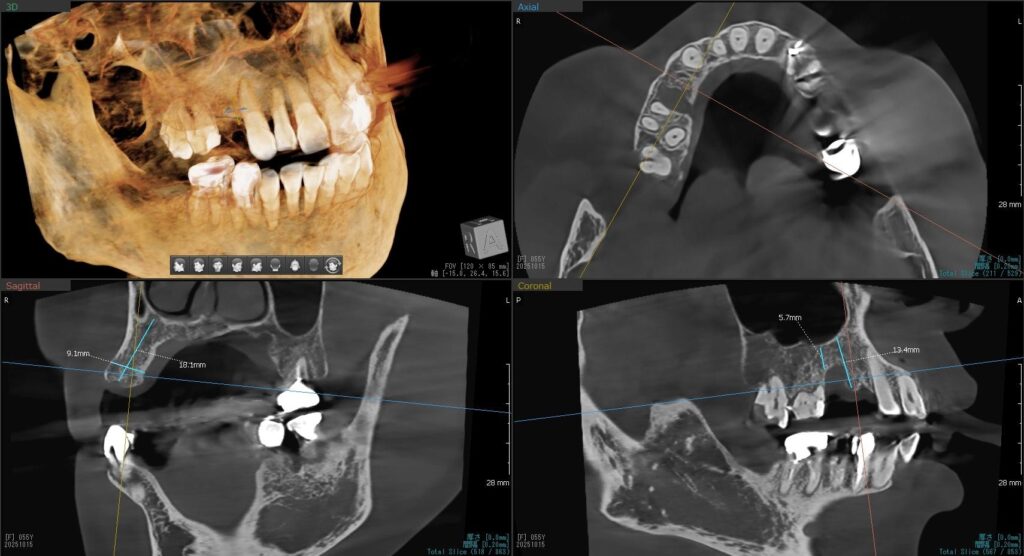

今回の患者様はインプラント植立を希望され、右上4番目・5番目の2本の植立が決まりました。

ドリルの先端を細い物から徐々に大きい物に変えながら、植立するインプラント体のネジの部分を除いた胴の部分の太さに合わせた大きさの穴を開けていきます。

開けた穴に、専用道具を使ってネジを締めるように長さ2センチ程のインプラントを骨に埋め込んでいきます。